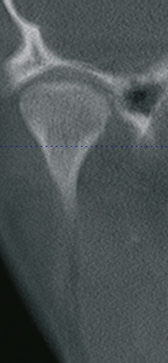

Die theoretische Unzulänglichkeit von Ausdrücken wie „die Zentrik“ oder „die zentrische Kieferrelation“ lässt sich gut an einem Patientenfall darstellen. In der Praxis stellte sich eine Patientin mit Kopfschmerzen und einem Knacken im linken Kiefergelenk vor. Nach klinischer Funktionsanalyse, Axiografie (Freecorder BlueFox, orangedental/Biberach a. d. Riß; Abb. 2) und Gelenkraumdiagnostik unter Einbeziehung eines DVTs wurde die Diagnose „CMD mit Myopathie, Arthropathie (aDVmR links, beidseitige dorso-kraniale Kondylenverlagerungen) bei Kopfschmerzen vom Spannungstyp und zervikozephalem Syndrom“ gestellt. Die Positionen beider Kondylen in der HIKP erwiesen sich als unphysiologisch und die zahnärztliche Therapie war daher primär darauf ausgerichtet, eine physiologische Kieferrelation mit physiologischen Kondylenlagen herzustellen. Dabei wurden zwei Methoden verwendet, die Registrierung der „physiologischen Zentrik“ [10] und die konstruktive Wiederherstellung der funktionellen Gelenkräume [12]. Die Resultate beider Methoden werden im CAR-Gerät sichtbar gemacht.

Die Konstruktion der funktionellen Gelenkräume beruht auf der Wiederherstellung minimaler Gelenkräume, ohne die der Kondylus sich nicht physiologisch bewegen kann. Zur Ermittlung dieser funktionellen Gelenkräume wird auf die Daten der klinischen Funktionsanalyse, der axiografisch ermittelten Gelenkbahnen (Abb. 8) und die der Gelenkraumanalyse (Abb. 9) zurückgegriffen. All diese Daten werden analysiert und interpretiert, um so eine physiologisch-therapeutische Kondylenlage zu konstruieren [12]. In diesem Fall wurden zusätzlich die dreidimensionalen Gelenkdaten einer DVT-Aufnahme mit einbezogen, dargestellt in den Abb. 10 und 11. Es zeigte sich eine Kondylenpositionsklasse CP 2 [13].